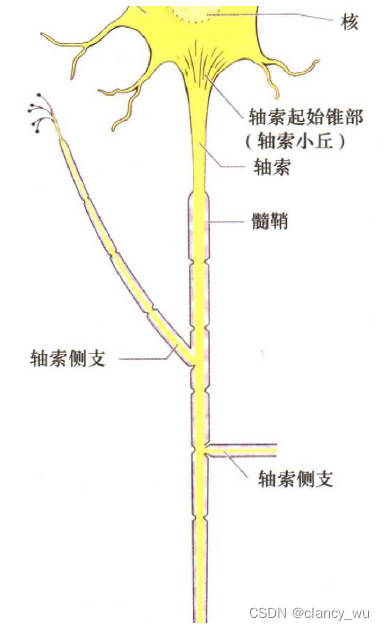

这种现象在大脑里也是存在的,因为大脑传递信息是通过神经元,而神经元的结构是树突和轴突组成,轴突就是方向性的连接。

在纤维束中,分子的扩散是各向异性的(anisotropic),水和液体和灰质是各向同性的(isotropic)。这很好理解,简单说就是纤维束中的分子运动只能朝着纤维束的方向扩散(轴突),脑脊液中的分子运动可以朝着周围随意运动,向各个方向运动的概率是相同的,这就是各项异性和各项同性的简单理解。这个是DTI分析的基本知识和背景。